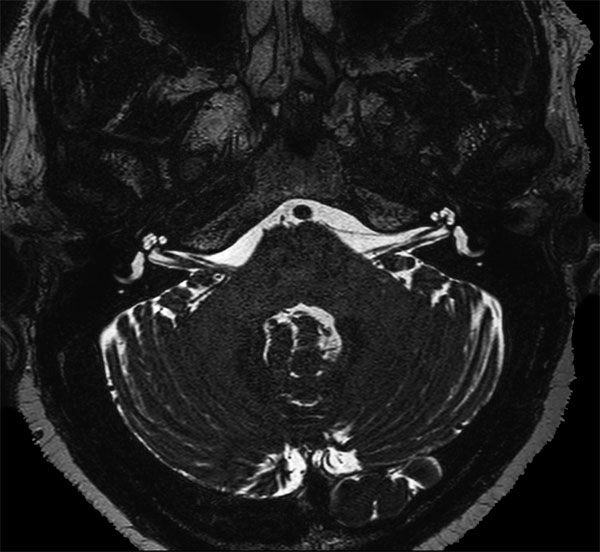

dS SENSE in Brain Imaging

Used Solution

• Clinical Application